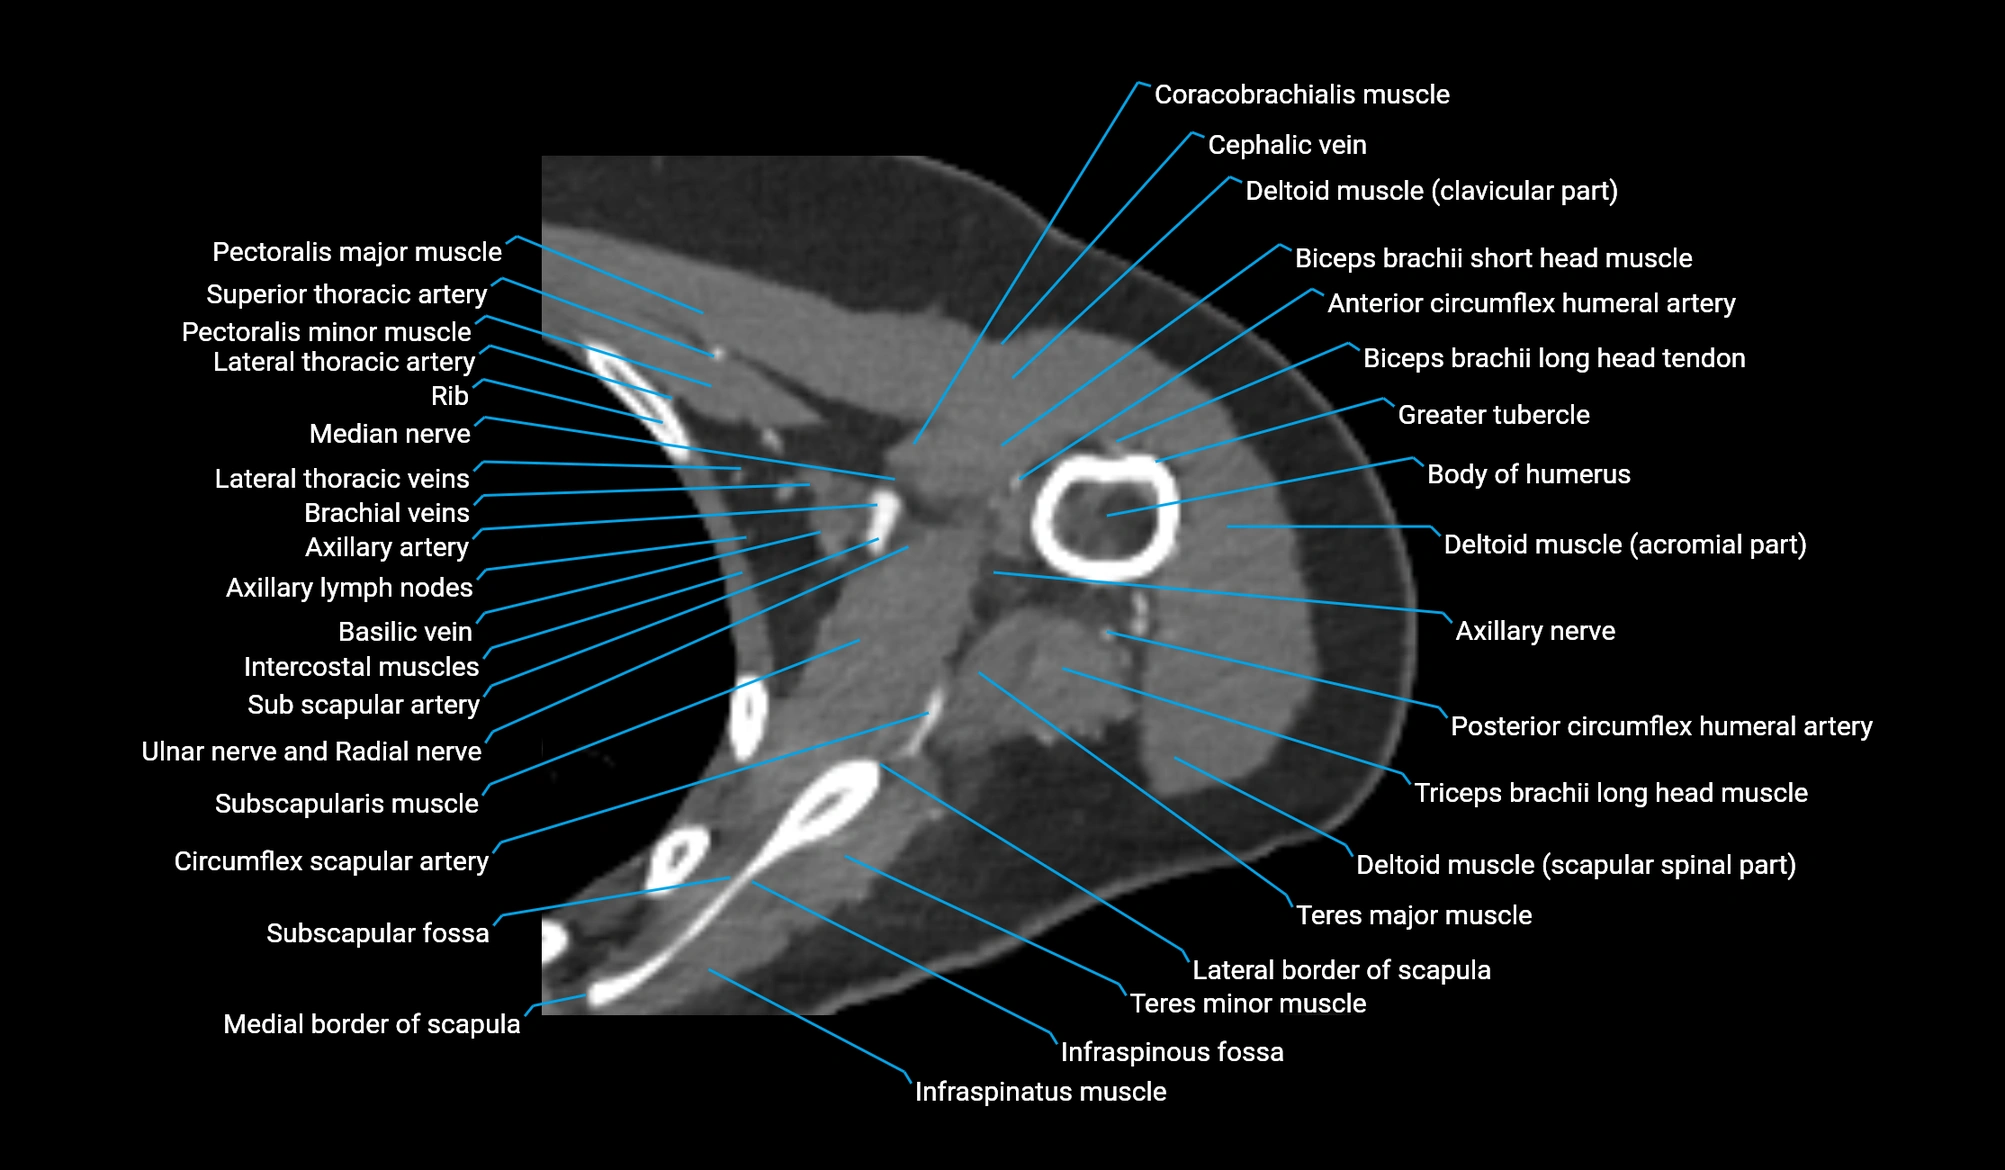

CT image